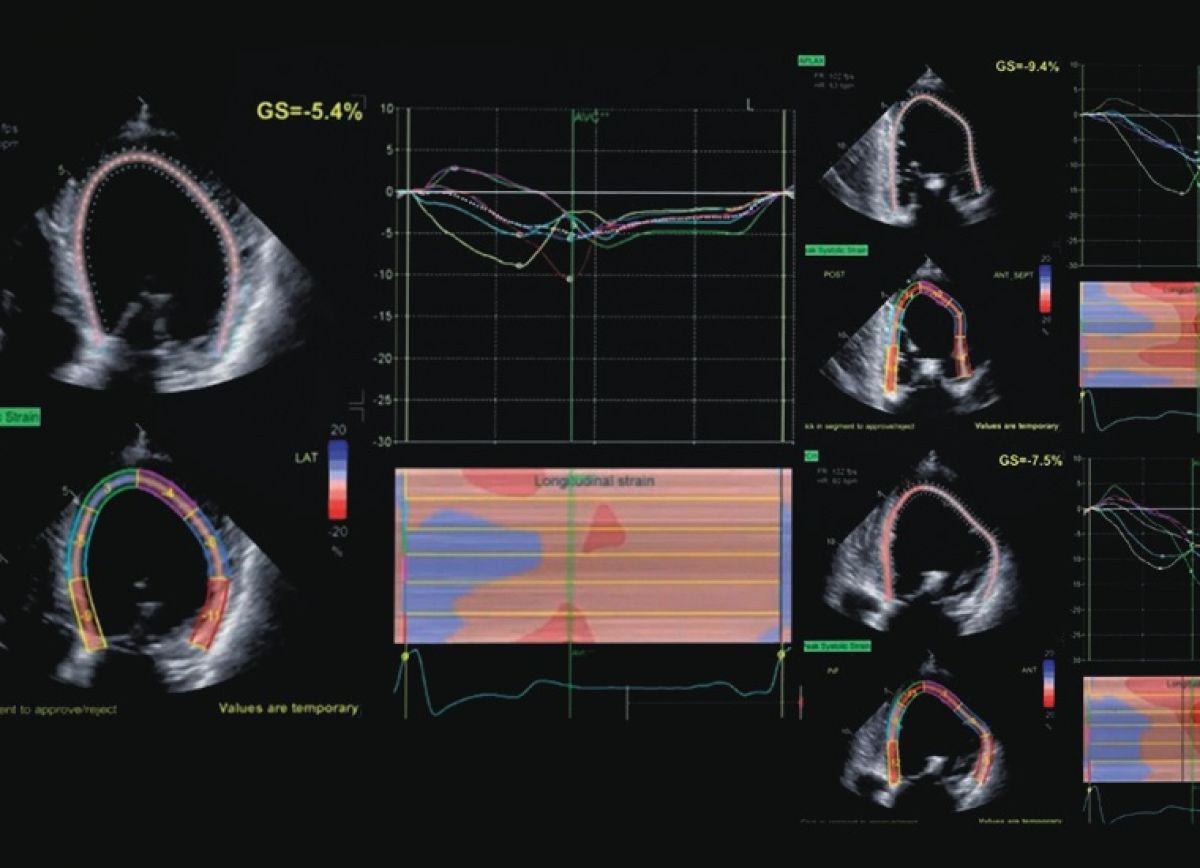

Ocena odkształcenia podłużnego mięśnia lewej komory